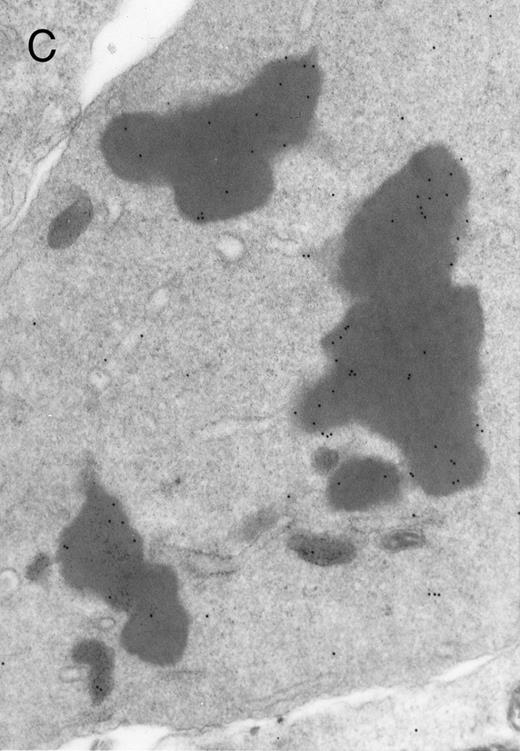

In both cases no. 1 and no. 2, electron microscope studies demonstrated electron-dense inclusions in 30% of early and late polychromatic erythroblast sections and many marrow reticulocytes. In ultrathin sections that reacted with monoclonal antibodies to either α- or β-globin chains followed by gold-labeled anti-mouse IgG, the density of gold particles over the majority of the inclusions was clearly greater than that over surrounding inclusion-free cytoplasm (Fig 3). By contrast, in sections from the two patients with β-thalassemia major, gold particles were concentrated over the inclusions following incubation with the antibody to α-globin chains, but not to β-globin chains (Fig 4A-C). The density of gold particles over inclusions in all control preparations was not greater than that over surrounding cytoplasm (Fig 4D).

Electron micrographs of erythroblastic inclusions from sections of marrow immunogold-labeled with mouse monoclonal antibody. Inclusions from case no. 1 show positive reactions with antibody against α-globin chains (A) and β-globin chains (B). Inclusions from case no. 2 show positive reactions with antibody against α-globin chains (C) and β-globin chains (D). Magnifications: A, × 32,000; B, × 38,000; C, × 32,000; D, × 37,000.

Prominent intra-erythroblastic inclusions were also present in both of these individuals (patients no. 1 and 2) with dominantly inherited β thalassemia. The percentage of polychromatic erythroblast sections containing inclusions in the two cases was 30%, which is considerably above the range (0.2% to 2.8%) previously reported in β-thalassemia trait.13 We have investigated the composition of the inclusions in cases no. 1 and 2 by immunoelectron microscopy using mouse monoclonal antibodies against human α- and β-globin chains and the immunogold technique. The intra-erythroblastic inclusions in the two cases reacted with both monoclonal antibodies to α- and β-globin chains, clearly indicating that these inclusions contained both types of chains. In contrast, the intra-erythroblastic inclusions found in homozygous β thalassemia reacted with the monoclonal antibody against α globin but not β-globin chains, confirming that they consisted only of precipitated α-globin chains. These data support the hypothesis that the cellular pathology underlying the dominantly inherited β thalassemias is related to the synthesis of highly unstable β-globin chains, which are not able to form functional tetramers. These abnormal β-chain variants precipitate intracellularly together with the concomitant excess α-globin chains to form large inclusions, which leads to more severe ineffective erythropoiesis than in heterozygous β thalassemia, in which much smaller amounts of precipitated globin chains are found.17